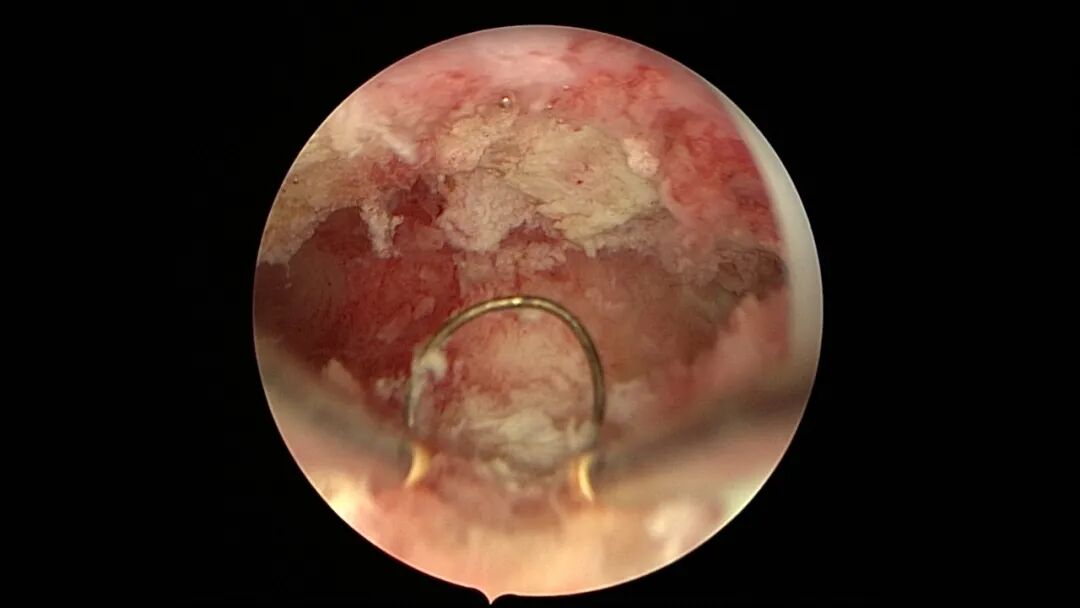

第五次宫腔镜:2023年8月初自然妊娠,药流不全,2023年8月底行宫腔镜清除残留胚物。宫腔下段前壁及左侧壁胚物残留,胚物与宫壁粘连,双侧输卵管开口可见,内膜稍苍白。单极电切环切除残留胚物组织,恢复宫腔形态,宫腔注入防粘剂,未放置球囊,患者拒绝送病检。